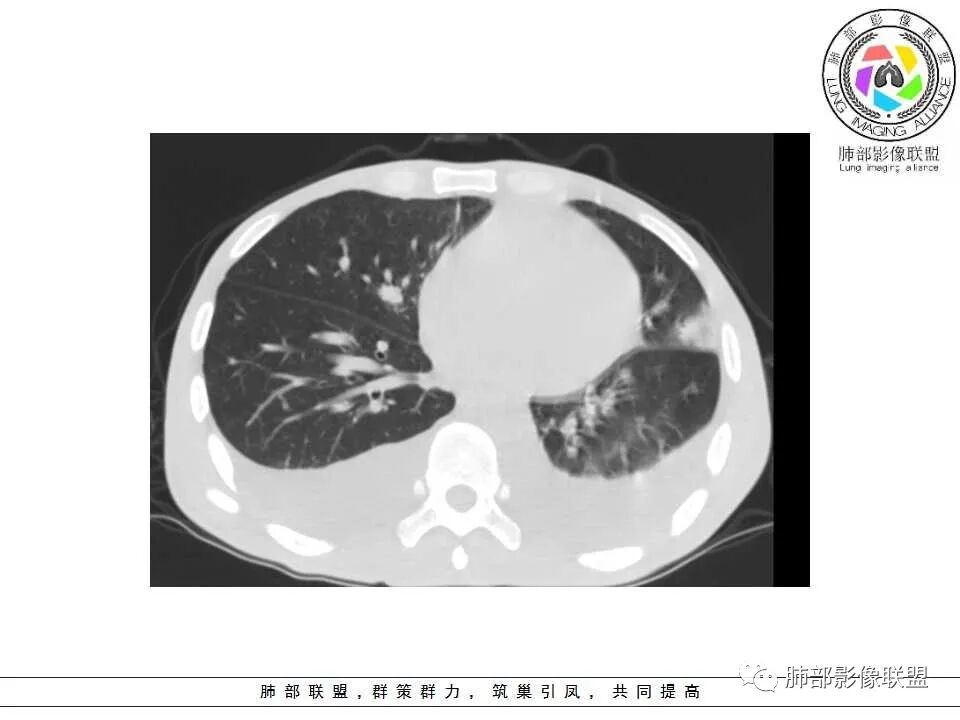

2.双肺散在不规则小片状影及结节影,部分可见磨玻璃晕。结节影边界较清楚。左肺片影边界不清,范围较大,支气管相关,支气管壁增厚不明显,病灶内见液化空洞。

4.脾脏明显增大,密度减低。肝脏未见异常密度影。

综合分析:

1.会是转移瘤吗?恶性肿瘤病史,双肺多发病灶,随机分布趋势,会想到肺转移瘤。

但转移瘤大多为边界清晰、比较规则的结节影,尤其是结肠癌转移,发现时结节还会较大,很少成片,与支气管关系密切者更为鲜见。

3.会是感染吗?双肺多发小片状影及结节影,支气管相关,可以符合感染。

哪种感染可能性较大?

3.肺炎型肺部影像学表现常为双肺多发片影,肉芽肿样结节影,边界相对清楚,可见磨玻璃晕,部分病灶可显示坏死空洞。部分病例出现胸水。支气管炎型病例可见较广泛支气管壁增厚。

4.应当注意肺外组织器官病灶的发现,如肝脏多发小脓肿及脾脏多发低密度结节影等,出现于白念珠菌的这些肺外小脓肿颇具特色,可以类似转移瘤的“牛眼征”,宜结合临床及病史综合判断。